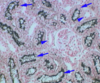

Label A-C

A: arcuate vessels

B: interlobular arteries

C: interlobar vessels